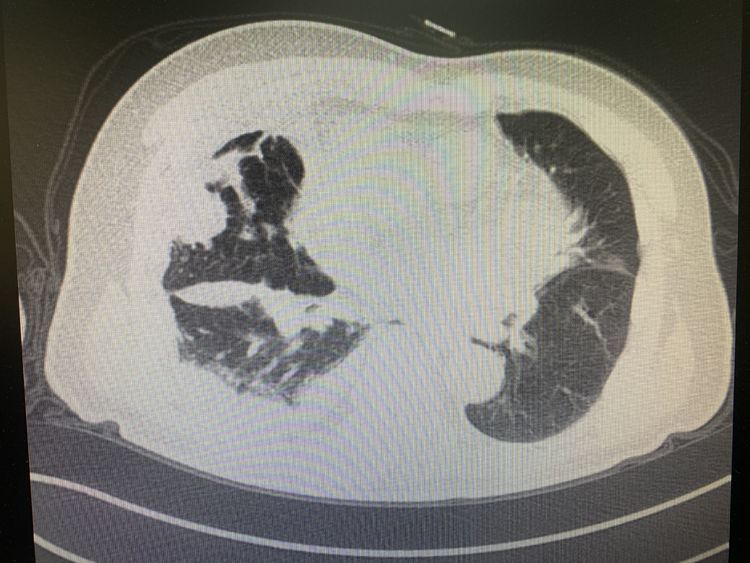

2020-04-10市九院老年病一科救治肺栓塞患者1例

75岁的患者王某,因胸闷、气短3天,发热1天入院在老年病一科接受治疗。患者持续端坐前倾位已有3天,且高度浮肿,由于对去医院治疗还存在顾虑,没有及时检查治疗。他既往... -